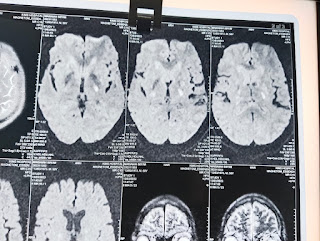

MRI

Impression:

Acute infarct in posterior limb of left internal capsule

Old lacunar infarct in left side of pons

Few microhemorrhages in bilateral cerebral hemispheres.

CONFIRMED DIAGNOSIS:

Cerebrovascular accident with Right sided hemiparesis ,

Acute infarct in posterior limb of internal capsule.